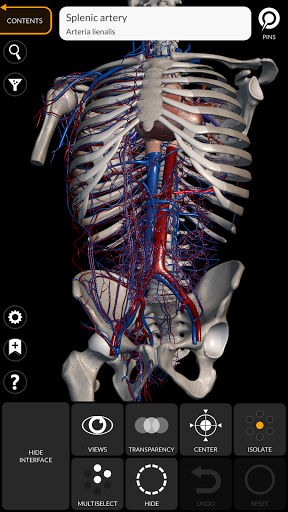

"Anatomía - Atlas 3D" permite estudiar la anatomía humana de forma fácil e interactiva.

A través de una interfaz sencilla e intuitiva es posible observar cada estructura anatómica desde cualquier ángulo.

Los modelos anatómicos 3D son especialmente detallados y con texturas de hasta una resolución de 4k.

La subdivisión por regiones y las vistas predefinidas facilitan la observación y el estudio de partes individuales o grupos de sistemas y las relaciones entre los diferentes órganos.

• Sistema cardiovascular • Sistema

nervioso • Sistema respiratorio • Sistema digestivo • Sistema urogenital (masculino y femenino) • Sistema endocrino • Sistema linfático • Sistema ocular y auditivo CARACTERÍSTICAS • Interfaz sencilla e intuitiva • Rotar y hacer zoom en cada modelo en el espacio 3D • Opción para ocultar o aislar uno o varios modelos seleccionados • Filtro para ocultar o mostrar cada sistema • Función de búsqueda para encontrar fácilmente cada parte anatómica • Función de marcador para guardar vistas personalizadas • Rotación inteligente que mueve el centro de rotación automáticamente • Función de transparencia • Visualización de músculos a través de niveles de capas desde las superficiales hasta las más profundas • Al seleccionar un modelo o un pin, aparece el término anatómico relacionado • Descripción de los músculos: origen, inserción, inervación y acción • Mostrar/ocultar interfaz de usuario (muy útil con pantallas pequeñas) MULTILINGÜE • Los términos anatómicos y la interfaz de usuario están disponibles en 11 idiomas: latín, inglés, francés, alemán, italiano, portugués, turco, ruso, español, Chino, japonés y coreano • Los términos anatómicos se pueden mostrar en dos idiomas simultáneamente REQUISITOS DEL SISTEMA • Android 8.0 o posterior, dispositivos con al menos 3 GB de RAM Reversi

• Sistema cardiovascular